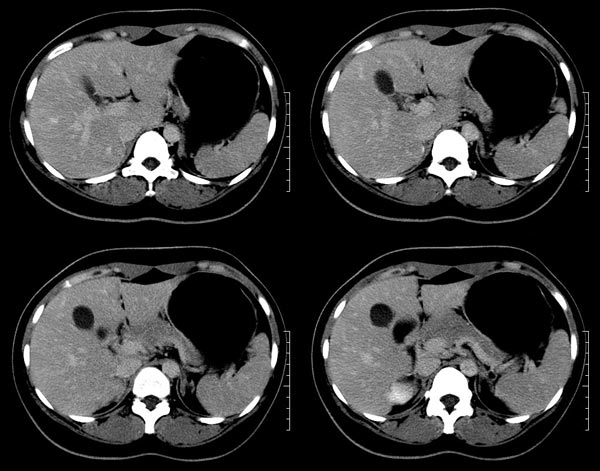

以下是引用52yingxiang在2007-9-16 10:16:00的发言:[br]肝脏局灶性结节增生影象表现(fnh)[br][br]肝脏局灶性结节增生是一种少见的肝脏良性肿瘤,可表现为边界清楚并无包膜的实质性肿块。病变大小不一,多系单发,亦可多发。组织学上是由结构紊乱的肝细胞、库普弗细胞、胆管、血管和粗厚的纤维性间隔所组成。[br]局灶性结节增生的ct表现可归纳为6点:[br]1、密度变化是其特征性改变,平扫多为低密度,少数为等密度,无论增强的早期或晚期均可能呈等密度,增强扫描有助于发现平扫为等密度的病灶;[br]2、中心疤痕,部分病灶在动态ct扫描时早期可看到中心疤痕增生性结节性病灶,ct血管造影也可看到普通ct不能显示的车轮状血管和车轴样改变;[br]3、纤维性分隔影,平扫为低密度,增强后为高密度;[br]4、包膜征象,增强后可以出现包膜强化,晚期较明显;[br]5、邻近血管的改变,主要是肝静脉受压,是发现等密度病变的重要依据;[br]6、瘤内胆管显影,这需要在胆管造影增强的情况下方能显示,出现率不高。[br][br]本例特点: 平扫低密度,增强动脉期明显强化,中心点条状低密度影(考虑纤维瘢痕),静脉期及延时期明显退减并与肝呈等密度,但中心仍可见低密度灶。[br]考虑肝脏局灶性结节增生(fnh)